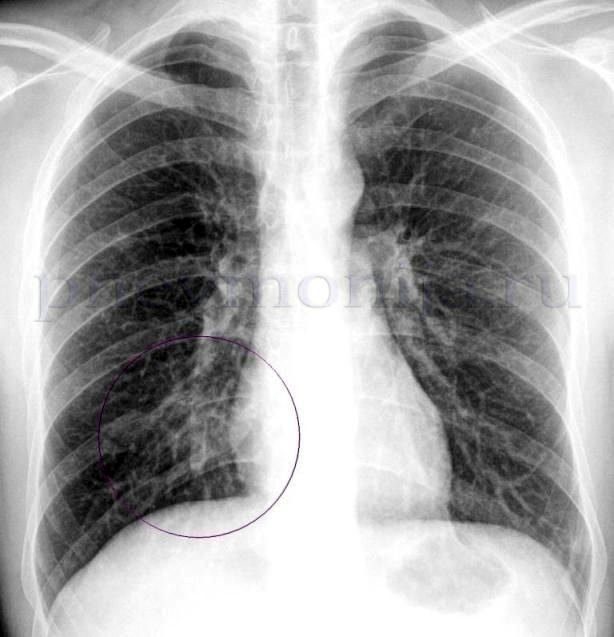

Диагноз основывается на симптомах острой инфекции дыхательных путей и наличии затемнения при рентгенологическом исследовании органов грудной полости, которое не связанное с какой-либо другой причиной (например, кардиогенный отек легких).

1. рентгенографию органов грудной клетки – выявляет затемнение ткани легкого;

M (multilobar infiltration) Мультилобарная инфильтрация на рентгенограмме легких 1